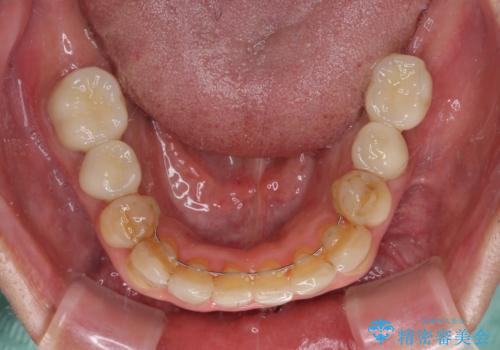

全体的に中等度の歯周病と診断されたため、歯周外科処置やインプラントによる咬合回復から進めて行き、矯正治療による歯列改善を行った後にオールセラミッククラウンにて補綴することとしました。

矯正治療を希望して来院されましたが、歯周病を併発していたため、矯正治療開始前の処置が非常に多くなりました。特に歯槽骨の再生治療を行ったため、外科処置後の静置期間が長くなり、4年弱の治療期間となりました。

治療後には咬みやすさだけでなく、前歯が大変審美的に仕上がり、患者様には大変満足していただきました。